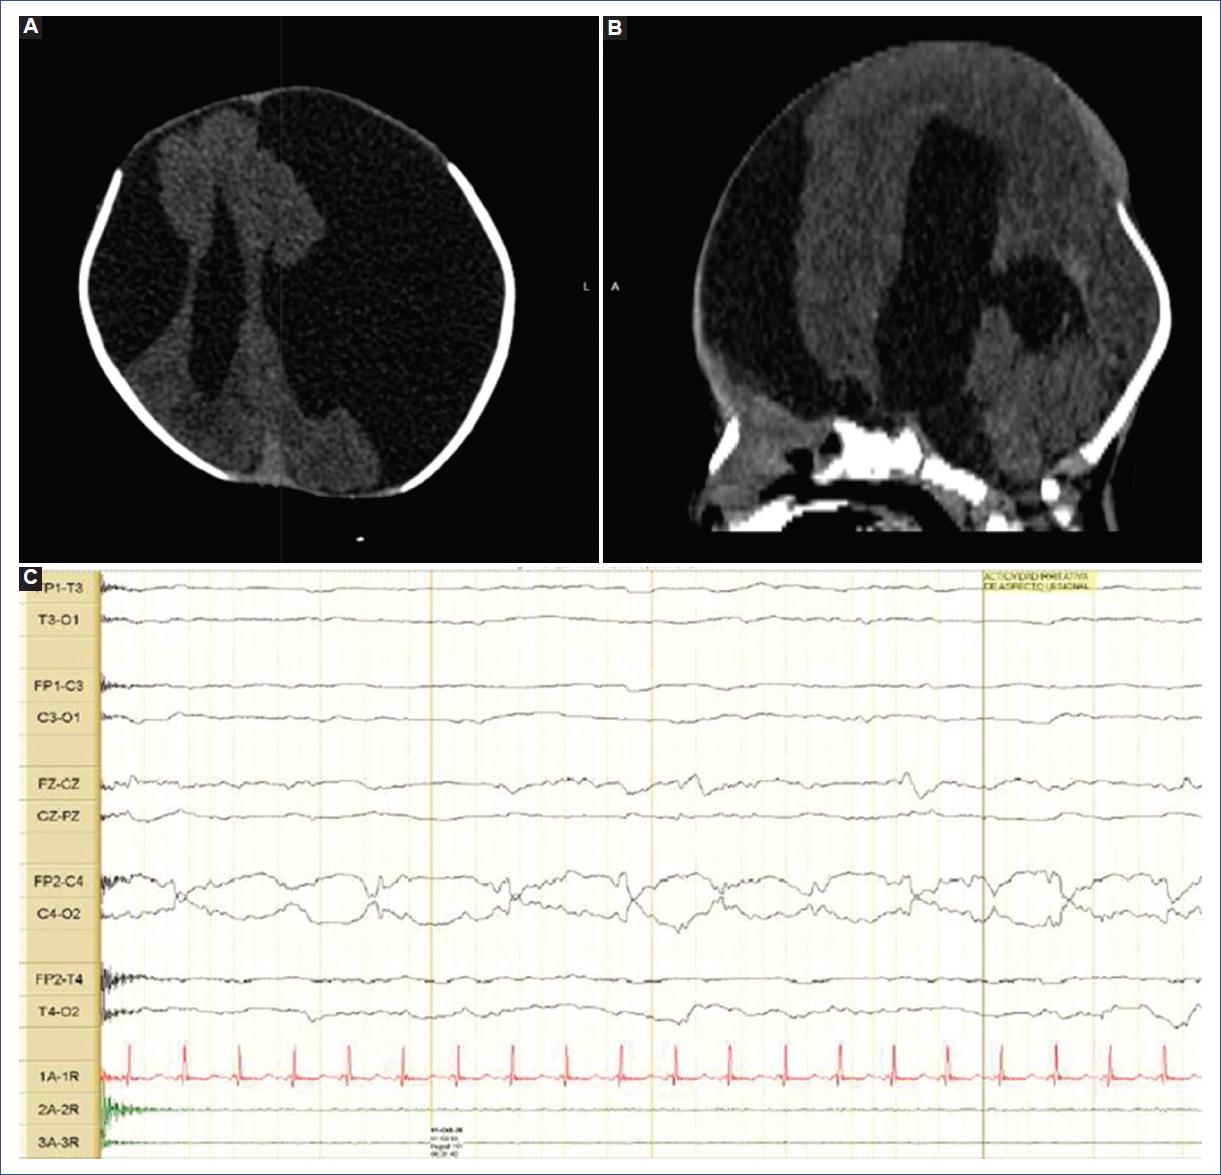

Por el compromiso neurológico, se realizó una tomografía computarizada (TC) de cráneo simple que evidenció una hendidura que comprometía las regiones frontotemporales de ambas convexidades, comunicación del espacio subdural con los ventrículos laterales y ausencia del septo pelúcido, y el tercer ventrículo dilatado. Con estos hallazgos se estableció el diagnóstico de esquizencefalia de labio abierto bilateral (Fig. 1 A y B). Presentó crisis epilépticas dentro de las primeras 24 horas de vida, por lo cual se inició manejo con fenobarbital con dosis de impregnación de 20 mg/kg y luego de mantenimiento entre 5 y 7.5 mg/kg/día. Se realizó un videoelectroencefalograma que mostró pobre diferenciación del ciclo sueño-vigilia, actividad epileptiforme de aspecto lesional central derecha y dos progresiones eléctricas bilaterales hasta por 20 segundos con manifestación clínica de movimientos clónicos del brazo izquierdo (Fig. 1C). Por lo anterior, se adicionó levetiracetam a dosis de 30 a 60 mg/kg/día, pero persistió la clínica de crisis epilépticas, por lo cual se adicionó vigabatrina a dosis de 50 mg/kg/día cada 12 horas. Por su inestabilidad clínica no se pudo realizar resonancia magnética (RM) cerebral. Los estudios complementarios, como ecocardiograma y ecografía abdominal, fueron normales. La valoración de oftalmología reportó el hallazgo de sinequias posteriores, pupila fija adherida al cristalino e hipoplasia del nervio óptico bilateral. Fue valorado por genética, donde solicitaron cariotipo bandeo G como estudio inicial, el cual fue 46,XY. Durante su estancia cursó con trastorno grave de la succión y la deglución, y convulsiones recurrentes de difícil manejo. Teniendo en cuenta el deterioro clínico, el compromiso grave por TC y el mal pronóstico funcional del paciente, el caso fue llevado a junta de ética, donde se determinó iniciar cuidado paliativo y 33 días después del ingreso falleció.

Figura 1 Caso 1. A y B: tomografía computarizada de cráneo simple, cortes axial y sagital. Se observan una hendidura que compromete las regiones frontotemporales de ambas convexidades (A), comunicación del espacio subdural con los ventrículos laterales y ausencia del septo pelúcido; imágenes compatibles con esquizencefalia de labio abierto bilateral con tercer ventrículo dilatado (B). C: videoelectroencefalograma con registro de actividad interictal de ondas agudas y asimetría central derecha con posterior evidencia de evoluciones bilaterales hasta por 20 segundos; clínicamente, realización de movimientos clónicos del brazo izquierdo.